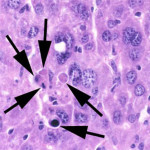

Un grupo de investigadores del Instituto Dana-Farber del Cáncer, dirigido por el Dr. Loren Walensky, desarrolló un compuesto de modelado directamente desde pro-apoptótica del dominio de la muerte de BCL-2, el dominio BH3 BIM. Este compuesto, conocido como un grapado péptido BIM BH3, se encontró que se unen competitivamente con proteínas anti-apoptóticos y condujo a la apoptosis mejorada en las células cancerosas. También demostraron que el crecimiento del tumor en ratones fue suprimida por el compuesto BIM BH3 y que el nuevo compuesto trabaja en sinergia con otros agentes farmacéuticos que promueven la apoptosis. Los efectos terapéuticos potenciales de BIM BH3 se muestra aún más por la activación de la muerte celular en un modelo de tumor de leucemia mieloide aguda en ratones con efectos secundarios poco sobre el tejido circundante.